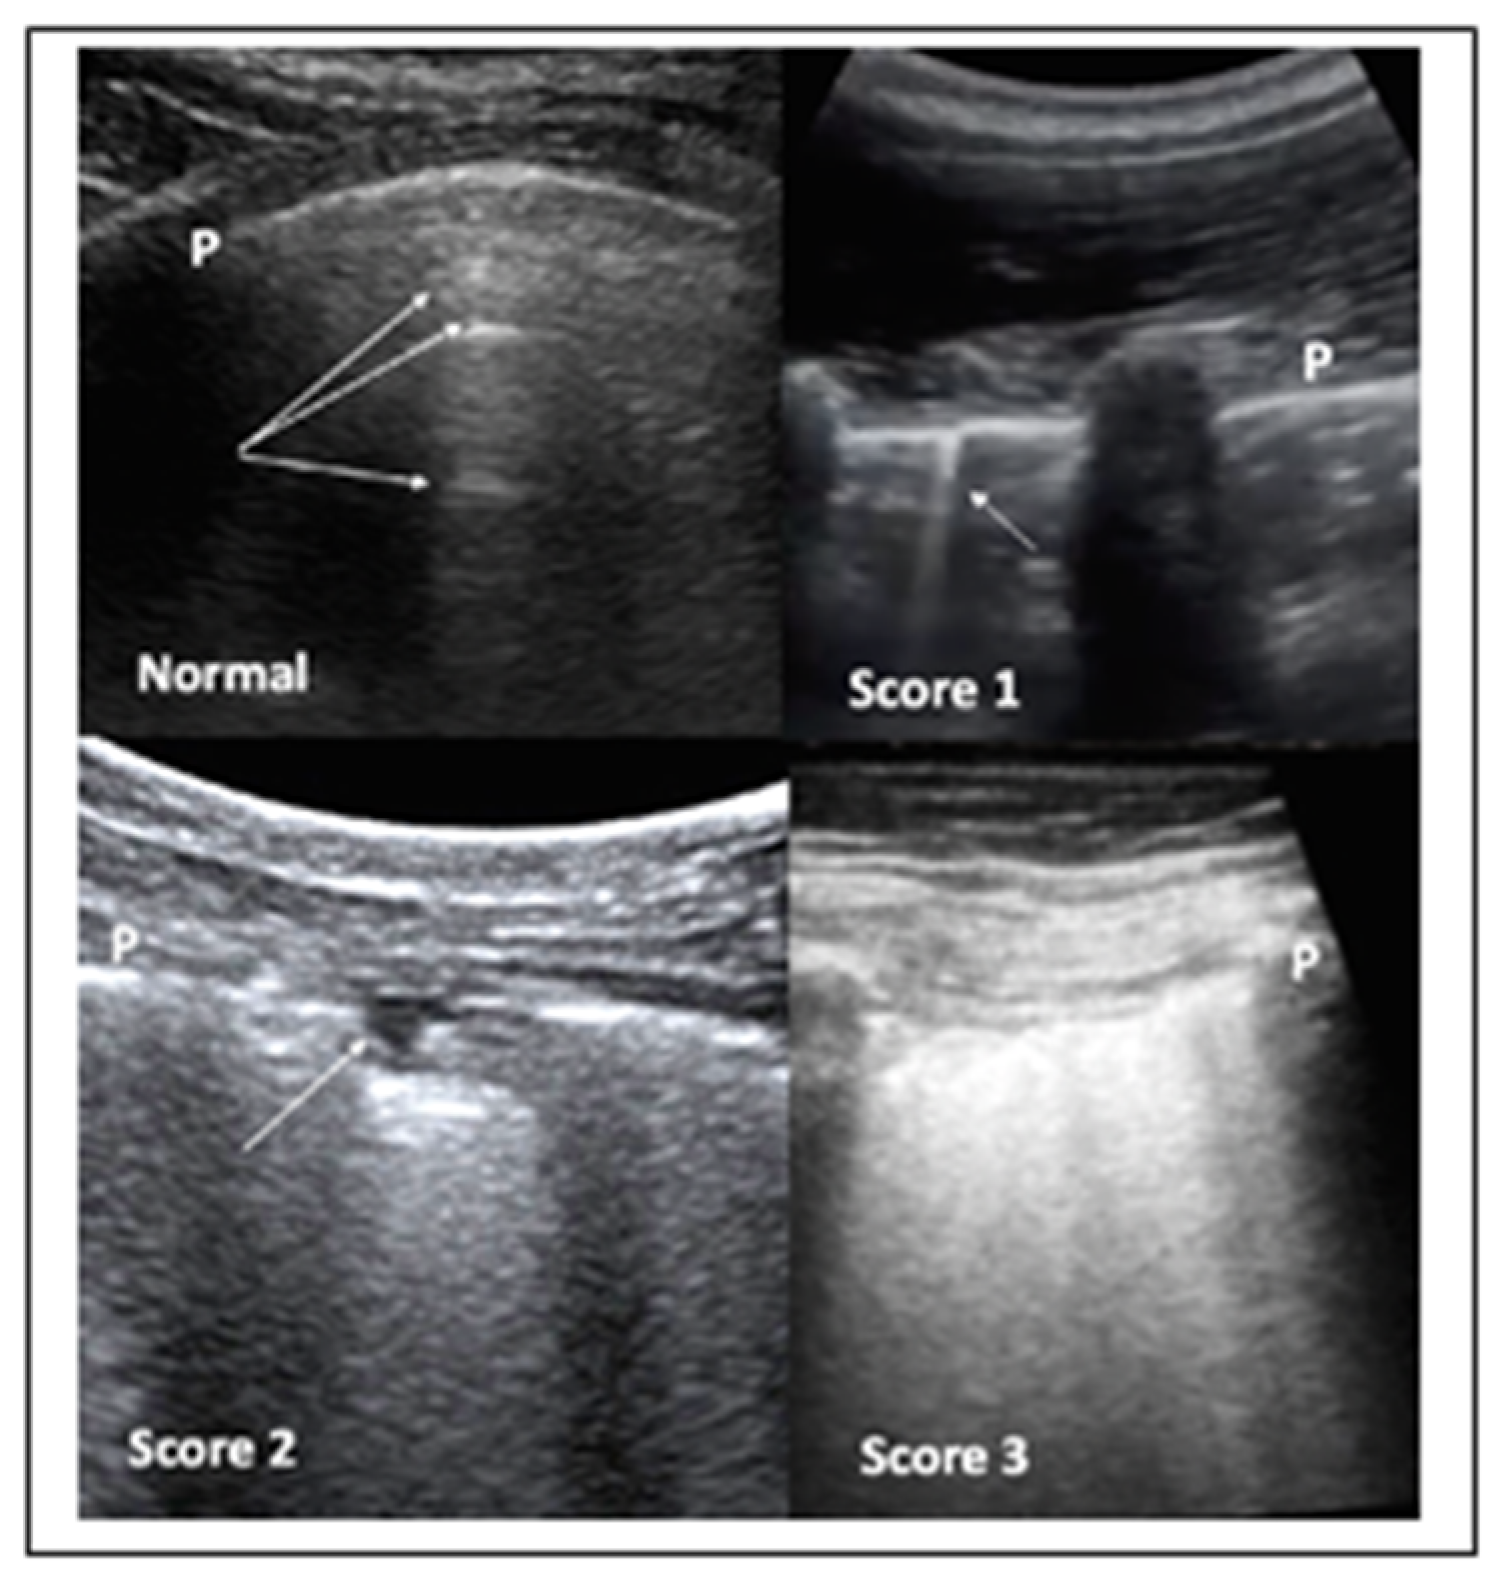

It has been also suggested that LUS should involve two operators in the acquisition protocol in order to reduce their exposure time to COVID-19 patients, with the first scanning and the second one storing the images. Both convex and linear probes can be used. Moreover, the standard LUS investigation is composed by 14 intercostal windows, seven for each side: three posteriorly along the paravertebral line; two laterally along the mid-axillary line; two anteriorly along the mid-clavicular line, these latter ones below and above the inter-nipple line, respectively. The LUS in patients not able to maintain a sitting position can be performed in lateral decubitus. COVID-19 pneumonia can be also scored for severity by LUS (Figure 3).

Figure 3.

LUS aspects of COVID-19 pneumonia. Top left panel—LUS in normal cases. The pleura line (P) is sliding, mobile at breathing, and hyperechoic. The arrows indicate the A lines, which are horizontal, not mobile lines below the pleura line. Top right panel—LUS in COVID-19 patient: the presence of irregularities of the pleura line (P) coupled with vertical, comet-like, mobile B lines (arrow) become apparent. These findings are frequently bilateral and alternate with areas of normality, as shown in this panel. Bottom left panel—LUS in COVID-19 patient: the pleura line P is broken. Subpleural triangular dark area (arrow) with a hyperechoic floor is defined a subpleural consolidation area. Bottom right panel—LUS in COVID-19 patient: the so-called “white lung”.